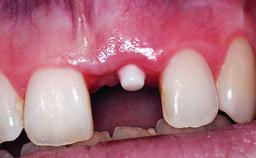

Replacement of an Upper Right Central Incisor with Root Resorption: Ridge Preservation, Early Placement of an RC Bone Level Implant

A 49-year-old female patient was referred for implant therapy to replace the upper right central incisor (tooth 11). The tooth had been assessed by an endodontist who diagnosed a vertical fracture of the root. The tooth had a hopeless prognosis and needed to be extracted. The patient was healthy and was not taking any medications. She was allergic to penicillin. The patient had high esthetic demands but her expectations were realistic. The extraoral examination revealed no facial asymmetries. The right temporomandibular joint demonstrated an opening click but was otherwise asymptomatic. The lip line was high with a significant gingival display.

Prosthesis Type FDP